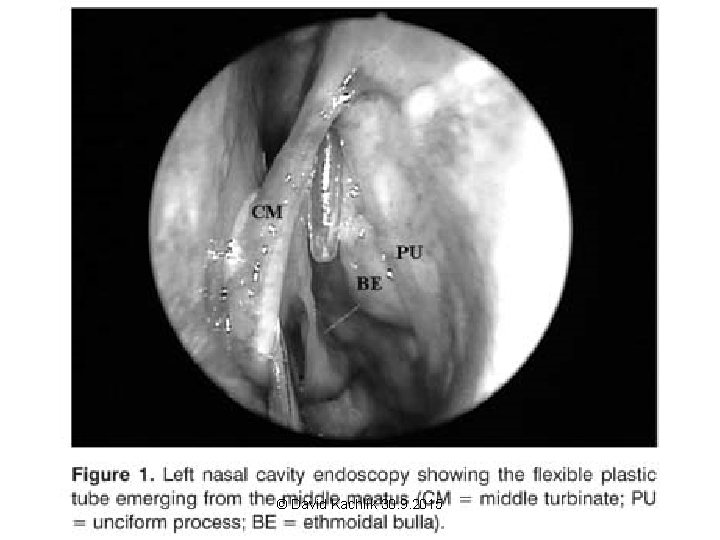

Middle nasal concha Lateral wall of the nasal cavity © David Kachlík 30. 9. 2015 Janoušek 2008 pro ECAE

© David Kachlík 30. 9. 2015 Janoušek 2008 pro ECAE

Nasal cavity + PS – clinical notes • epistaxis (bleeding from the nose) - locus Kiesselbachi, plexus Woodruffi, a. sphenopalatina • liquorrhea (the flow of the cerebrospinal fluid from the nose) – fractures of the base of the skull • sinusitis – puncture through the nasal cavity (for s. maxillaris at the level of the inferior nasal meatus – inferior antrotomy) – suction – FES (= functional endonasal surgery) • surgical approach to hypophysis through sinus sphenoidalis • sinus maxillaris – teeth • cellulae ethmoidales – orbit • examination: rhinoscopy (anterior, posterior), diaphanoscopy, X-ray, CT © David Kachlík 30. 9. 2015